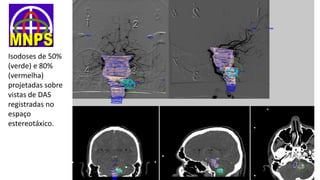

Isodoses de 50%

(verde) e 80%

(vermelha)

projetadas sobre

vistas de DAS

registradas no

espaço

estereotáxico.